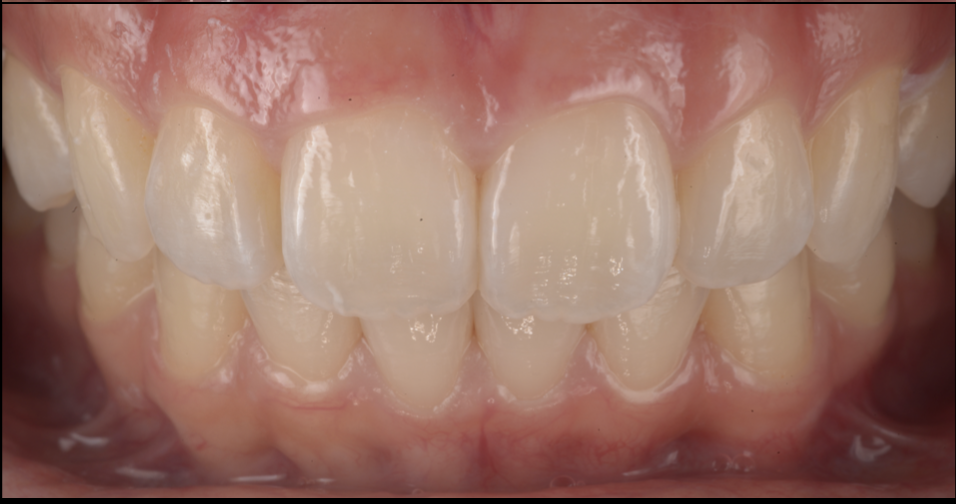

池袋で前歯のすき間をダイレクトボンディングで改善した症例|正中離開を削らずに自然に修復

- 担当医

- 生野誠

- 主訴

- 前歯のすき間が気になる

見た目を自然に整えたい

- 期間

- 1回

※症例により回数は異なります

- 費用

- 11万

- 治療内容

- 前歯2本に対するダイレクトボンディング

- 治療に伴うリスク

・経年的な着色が起こることがあります

・強い衝撃や咬み合わせによって欠けることがあります

・すき間の大きさや咬み合わせによっては、矯正治療や他の補綴治療が適する場合があります

・定期的なメインテナンスが必要です